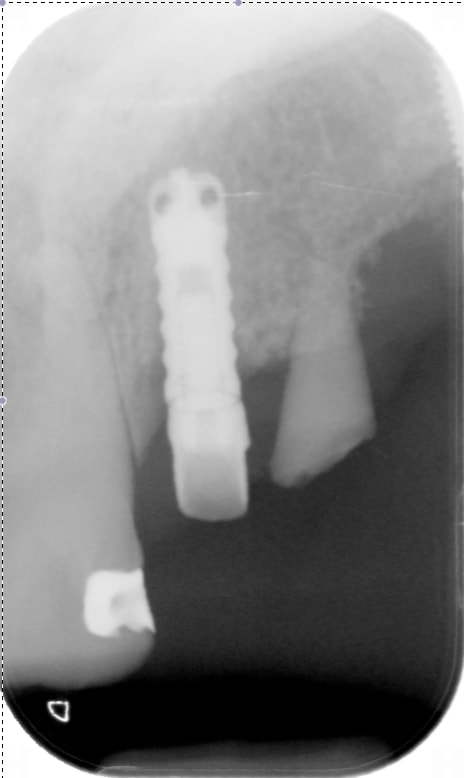

oups, radio oubliée !

tbr

https://www.spotimplant.com/fr/implants-dentaire/tbr/ide-hex-out

sans doute un TBR lisse, pour info le pas de vis est le même que les anthofit...